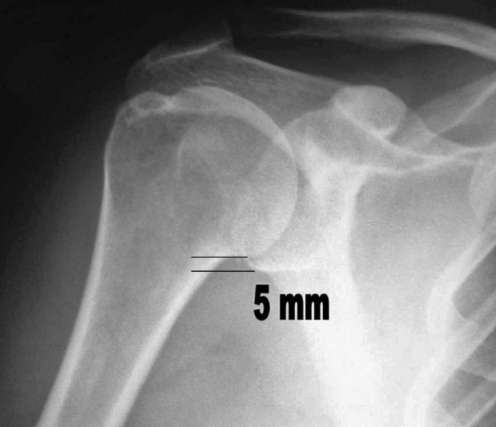

This retrospective study included 18 patients (13 female, 5 male) treated between June 2000 and March 2005. Preoperative and postoperative clinical examinations were performed, and the Constant test [8] was used to assess pain, mobility and strength. To check for possible osteoarthritis and proximal migration of the humeral head, antero-posterior radiography of the shoulder, in neutral rotation, was performed preoperatively and again at the end of the follow-up period. The presence of proximal migration was shown by an interrupted Shenton’s line extending from the glenoid rim to the humeral neck; migration was measured in mm up the humeral neck rather than in the subacromial space, which might have been modified by subacromial decompression (Figs. 1 and 2). Only one patient displayed mild arthrosis, with osteophytes less than 3 mm and no evidence of joint-line irregularities or subchondral sclerosis. Magnetic resonance imaging (MRI) was also performed preoperatively to check for tendon retraction, atrophy and fatty degeneration of the affected muscle (Fig. 3). Preoperative examination included the Napoleon test to rule out subscapularis tears; the findings were confirmed by MRI. Patients with subscapularis tears were excluded from the study.

Fig. 1.

Preoperative antero-posterior radiograph showing the interruption of Shenton’s line and migration of the humeral head

Antero-posterior radiography of the shoulder, in neutral rotation, showed a mean proximal migration of the humeral head of 5 mm (range 1–7 mm); postoperatively, the mean proximal migration was 1.8 mm (range 0–4 mm) (P=0.001), a decrease of 3.2 mm.